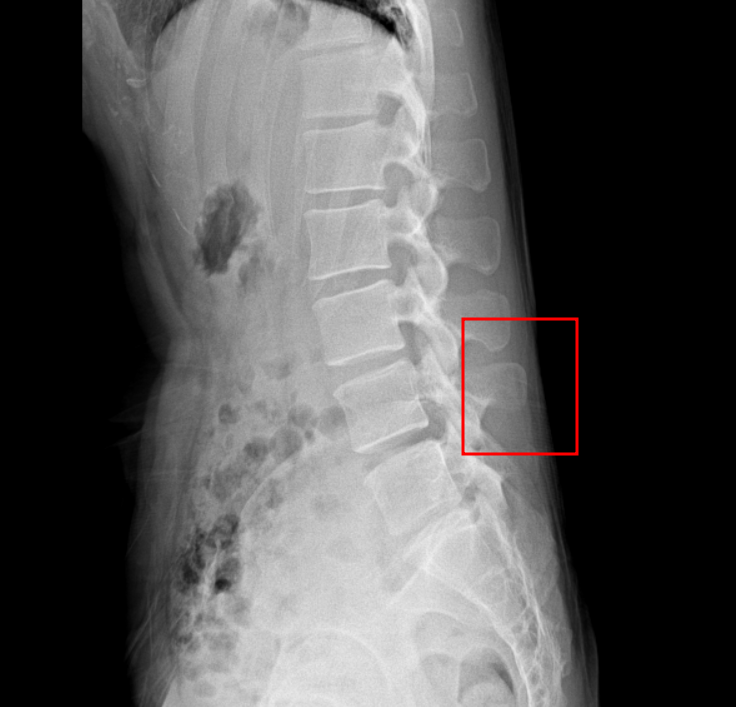

실제로 심한 염좌를 두차례나 겪고 한의원에서까지 그런 말을 하니 이전에 신경외과 소견은 어떻게 이해해야하는지 궁금합니다. 그리고 실제로 제가 스스로 허리를 만져보면 조금만 숙여도 뼈가 심각하게 튀어나오는데.. 이건 큰 문제 없는건지 궁금합니다. 엑스레이상에도 거의 가죽에 붙어있는것 같은데.. 이것은 문제가 없을까요?

글쎄요 특별한 이상이 없어보입니다. 뼈가 피부에 가까이 있어도 상관없습니다.한의사 선생님 의견은 제가 감히 드릴 말씀이 없습니다

현재 엑스레이에서는 문제가 없습니다. 허리 통증을 유발하는 것은 인대나 힘줄, 디스크 등의 손상이나 염증으로 치료를 하면서 증상이 호전되면 운동을 하시는 것이 필요하겠습니다.